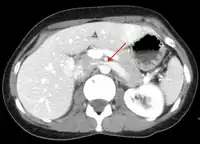

The nutcracker syndrome results from compression of the left renal vein between the aorta and the superior mesenteric artery.

The nutcracker syndrome (NCS) results most commonly from the compression of the left renal vein (LRV) between the abdominal aorta (AA) and superior mesenteric artery (SMA), although other variants exist.[1][2] The name derives from the fact that, in the sagittal plane and/or transverse plane, the SMA and AA (with some imagination) appear to be a nutcracker crushing a nut (the renal vein).

CT and MRI can be used afterward to confirm compression by the AA and SMA with comprehensive measurements of the abdominal vasculature. A "beak sign" can often be seen in CT scans due to the LRV compression. However, CT and MRI cannot demonstrate the flow within the compressed vein. These two modalities can be used to confirm other evidence for NCS such as back-up of blood flow into the ovarian veins.[11][6]